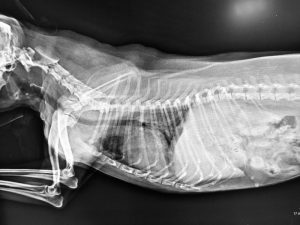

Radiology—DIGITAL RADIOGRAPHIC IMAGES

(Time to take the x-ray images is reduced significantly- less stress on the pet, less sedation time, smaller number of images taken, state of the art quality of images)